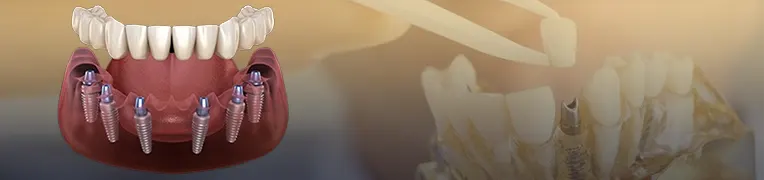

انواع ایمپلنت دندان شامل ایمپلنت اندوستال، ایمپلنت ساب پریوستئال و ایمپلنت زیگوماتیک هستند. هر کدام از این ایمپلنت ها برای مصرف مشخصی مورد استفاده قرار می گیرند. در میان تمام ایمپلنت های تولید شده هزینه ایمپلنت زیگوماتیک از دیگر ایمپلنت ها بیش تر است. از این نوع ایمپلنت نسبت به سایر ایمپلنت های موجود کم تر استفاده می شود.

تعداد ایمپلنتی که قرار است درون دهان قرار بگیرد، از دیگر عوامل مهم و تاثیر گذار در هزینه است. طبیعتا هزینه ای که باید برای قرار دادن یک ایمپلنت درون دهان قرار داده شود به مراتب کم تر از هزینه ای است که باید برای قرار دادن چند ایمپلنت درون دهان قرار گیرد.

هزینه ایمپلنت کامل فک بالا و پایین در ایران به عوامل متعددی مانند نوع برند ایمپلنت، تعداد پایههای مورد نیاز، وضعیت استخوان فک و نیاز به درمانهای جانبی مانند پیوند استخوان یا سینوس لیفت بستگی دارد.